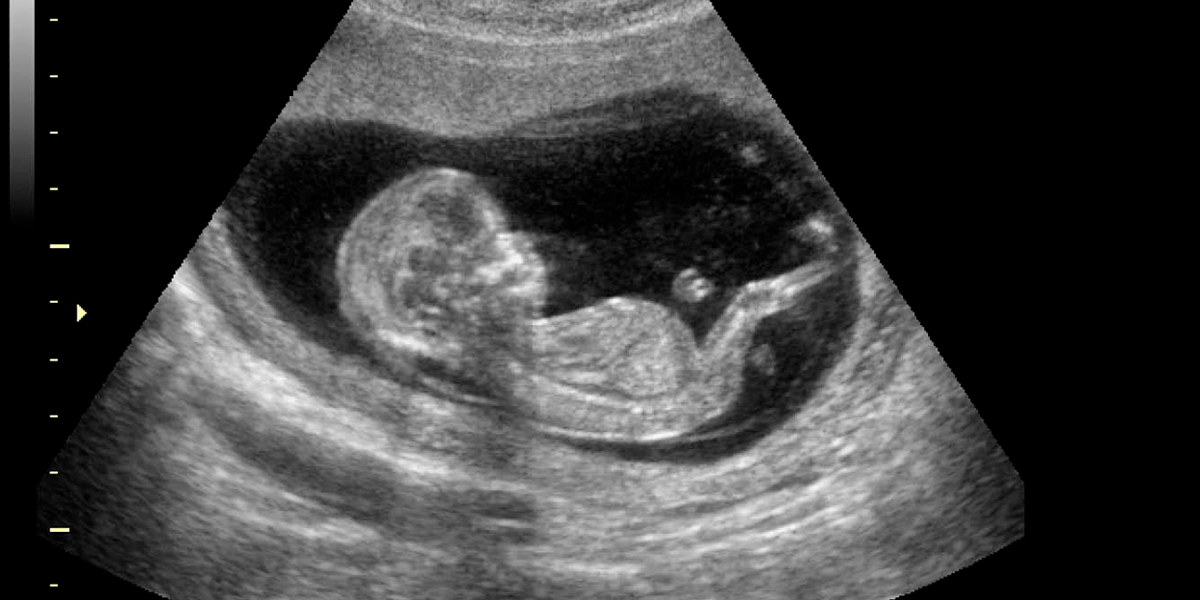

El fetus in fetu es una condición extremadamente rara en la que un gemelo se desarrolla dentro del cuerpo de su hermano en lugar de hacerlo de manera independiente en el útero materno. En el caso de Itzamara, un examen ecográfico de rutina reveló que un feto ‘parásito‘ estaba creciendo en su abdomen, alimentándose del corazón y los nutrientes de su hermana.

Durante el embarazo de Mónica Vega, madre de Itzamara, el feto parásito carecía de placenta, corazón y cerebro, y dependía completamente del cuerpo de su hermana para sobrevivir. El cirujano Miguel Parra explicó que este tipo de fenómeno ocurre cuando el embrión destinado a formar gemelos no se divide en el momento adecuado. «Es uno de los casos más raros que vemos en medicina materno-fetal«, declaró el doctor Parra.

El diagnóstico temprano fue crucial para la salud de Itzamara. De no haberse detectado a tiempo, el feto parásito podría haber debilitado gravemente a la niña, afectando su desarrollo y salud general. «Este parásito la habría desnutrido y podría haber causado daño en sus órganos«, advirtió el doctor Parra.